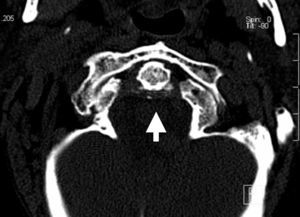

Axial skeleton affection due to chondrocalcinosis has been associated to calcium deposits in the intervertebral disc, the yellow ligament, the fact joints and even the sacroiliac joints. Calcification of the transverse ligament of the atlas (Figs. 1–3) is an infrequent manifestation and has been denominated the Crown Dens syndrome. It mostly constitutes an asymptomatic clinical picture but may be associated with episodes of acute cervical pain, stiffness and fever, with the added diagnostic difficulties of these cases.

We present the case of an 82-year-old woman who consulted us due to intense cervical pain which responded poorly to analgesics. She had a history of atrial fibrillation undergoing anticoagulation therapy, spondyloarthritis and radiologic chondrocalcinosis of the knees. Physical examination revealed spontaneous pain on the cervical spine, radiating to the occipital and mastoid regions, with stiffness and movement limitations due to pain, with no neurologic manifestations.

The Crowned Dens syndrome was described initially in 1985 by Bouvet et al.1,2 Diagnosis is based on the association of a compatible clinical picture and imaging findings, mainly calcium deposits in atlas-axis joint ligaments, visible on CT.3,4